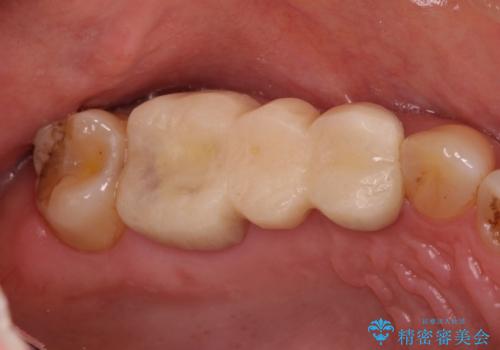

- 他院でブリッジの仮歯を入れたが、外れやすいため転院を希望された患者様です。

支台歯の形が角度が大きくついた形に形成してあり、外れやすい形になっていたため修正してから歯型をとりました。

- 36.3万円(ジルコニアクラウン10万円x3本)費用は治療当時の料金となります

根の治療のやり直しは特に行っていません。